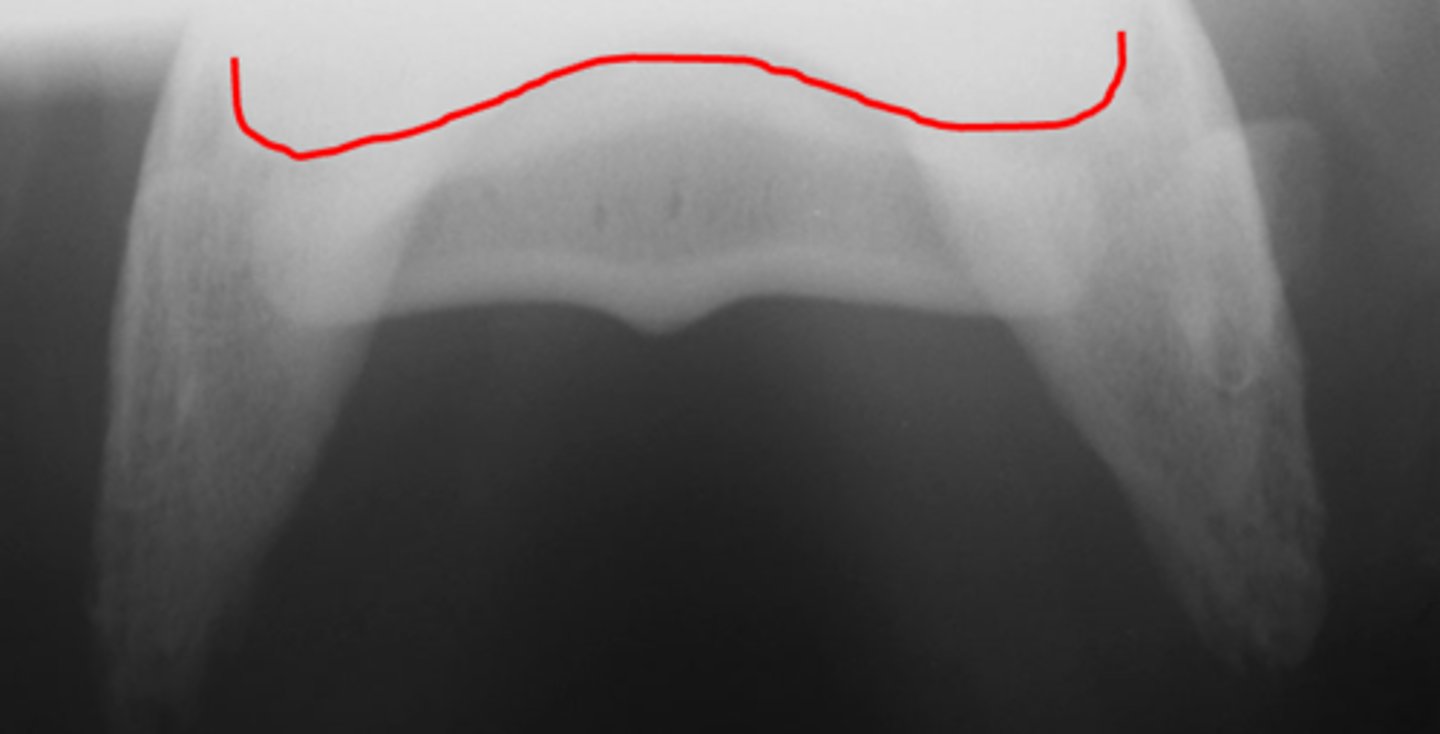

Pastern joint, LM

ID joint and view

Pastern joint, DP

ID joint and view

Short pastern (P2)

Long pastern (P1)

Pastern joint (proximal interphalangeal joint)

Long pastern (P1)

Short pastern (P2)

Extensor process of P3